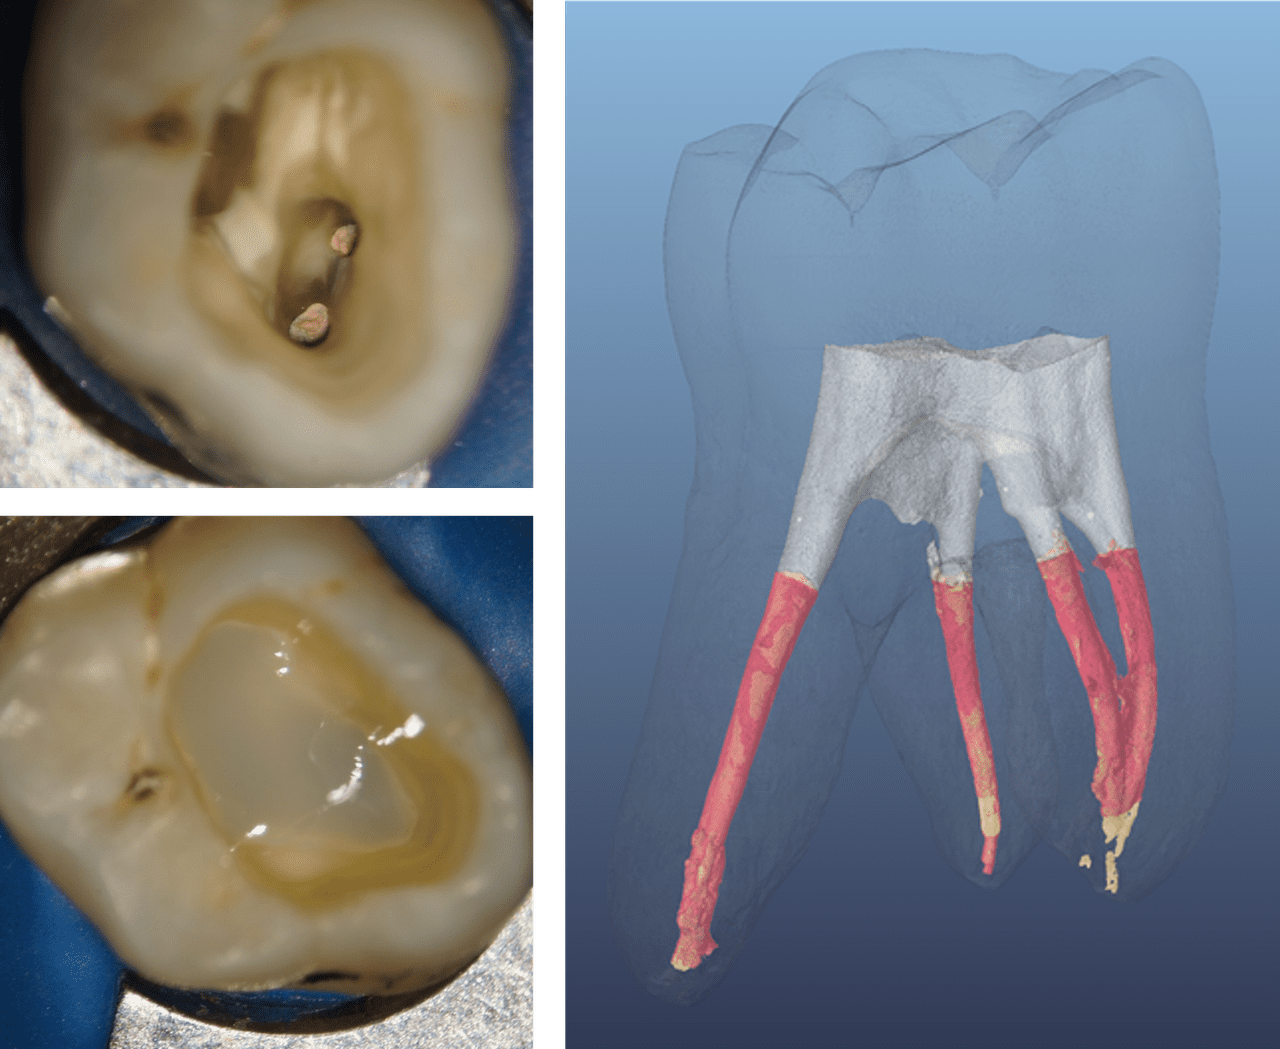

This conclusion finds support in several other reviews and retrospective studies7,8, leading to the conclusion by Atlas et al. that “[…] in ETT [endodontically treated teeth] with three or four coronal walls left, that is, at least one marginal ridge remaining, and no undermined cavity walls, direct adhesive restoration may be considered as an alternative to cuspal coverage.”5 Figure 2 provides a clinical example of both a Class I and II cavity in endodontically treated teeth, that are matching these criteria, allowing dental practitioners to place a less invasive and more cost effective direct restoration.

Figure 2: Endodontically treated posterior teeth with four and three coronal walls, and barely undermined residual tooth structure before and after direct restoration

(Courtesy of Dr. Marcus Holzmeier, Germany)